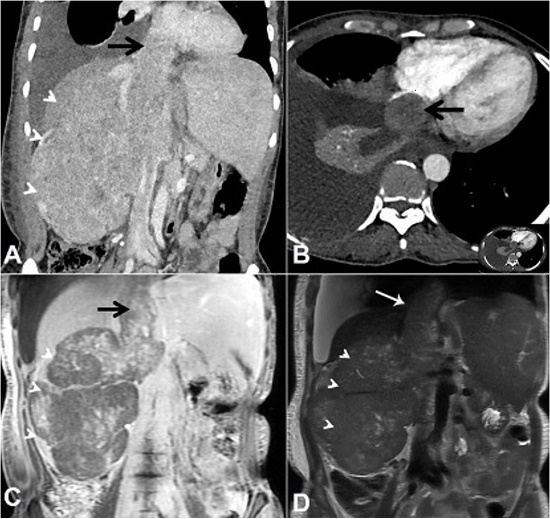

A 40-year old female presented with complaints of abdominal pain, predominantly on the right side, which gradually worsened along with occasional episodes of vomiting over 2 months. She also complained of a vague lump in the abdomen. Physical examination revealed respiratory distress, hypotension and bilateral pedal edema. On abdominal examination, a 15x15x10 cm lump was bimanually palpable over the right hypochondrium, epigastrium and the right lumbar region, which had a hard consistency and did not move with respiration. Right renal angle fullness was present. The routine investigations showed anemia, thrombocytopenia, hyperkalemia, and hyponatremia. The chest X-ray confirmed the presence of right-sided pleural effusion. The computed urotomography depicted a large heterogeneously enhancing mass with internal non-enhancing cystic to necrotic areas, measuring 10.5x11.9x16.0 cm in the right kidney. The lesion was invading and expanding into the renal vein, intrahepatic, suprahepatic IVC and reached up to the right atrium (Figure 1).

Possibility of a right renal cell carcinoma (RCC) with tumor thrombus into renal vein and IVC with wall invasion was considered. In view of radiological diagnosis of RCC, the patient was planned for an exploratory laparotomy. On the exploratory laparotomy, dense adhesions were present between the tumor, colon and infrarenal as well as suprarenal IVC. No dissection plane was found between IVC and the tumor.